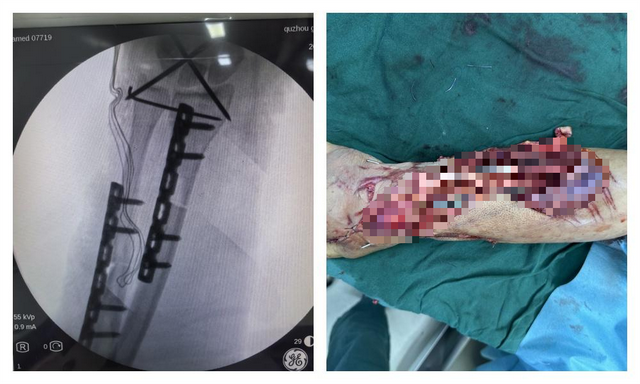

术中C臂机透视下,骨折端良好位置

右前臂离断,固定骨折断,内吻合神经血管肌腱